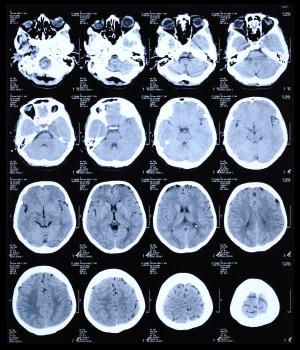

One two-dimensional x-ray image does not tell you much, but computed tomography takes scores of them and knits them together with a computer to generate a high-resolution 3D image.

CT is one of the two technologies that utilize ionizing radiation to create a picture of what is going on inside the body. At its simplest, a CT scan is an x-ray slice of the body. Slices are repeated along the area of interest, although for performance reasons multiple slice transmitters/receivers are typically grouped next to each other. The body can also be moved during exposure in order to create a “spiral” image that can be unwound into slices or a 3D view (see Figure 1).

Figure 1: CT scan of the human brain.